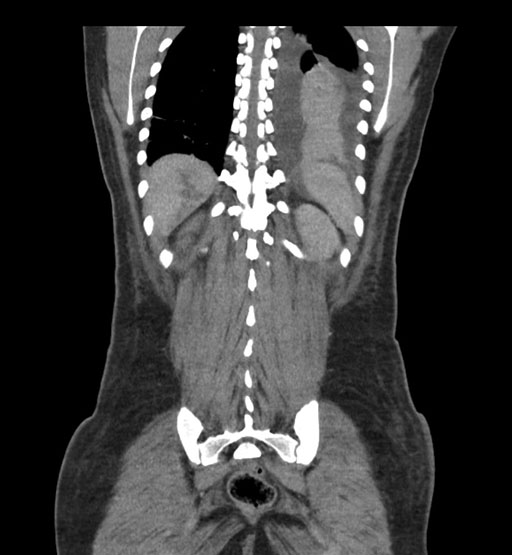

Vasculobiliary injury [M28]

Imaging Analysis

Look through the patient's CT scan to identify any areas of concern for the necessary procedure.

Coronal Arterial

Coronal Venous